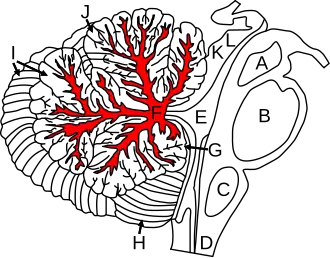

Figure shows cerebellum and surrounding regions; sagittal view of one hemisphere. A: Midbrain. B: Pons. C: Medulla. D: Spinal cord. E: Fourth ventricle. F: Arbor vitae. G: Flocculus. H: Tonsil. I: Posterior lobe. J: Anterior lobe. K: Inferior colliculus. L: Superior colliculus. | |